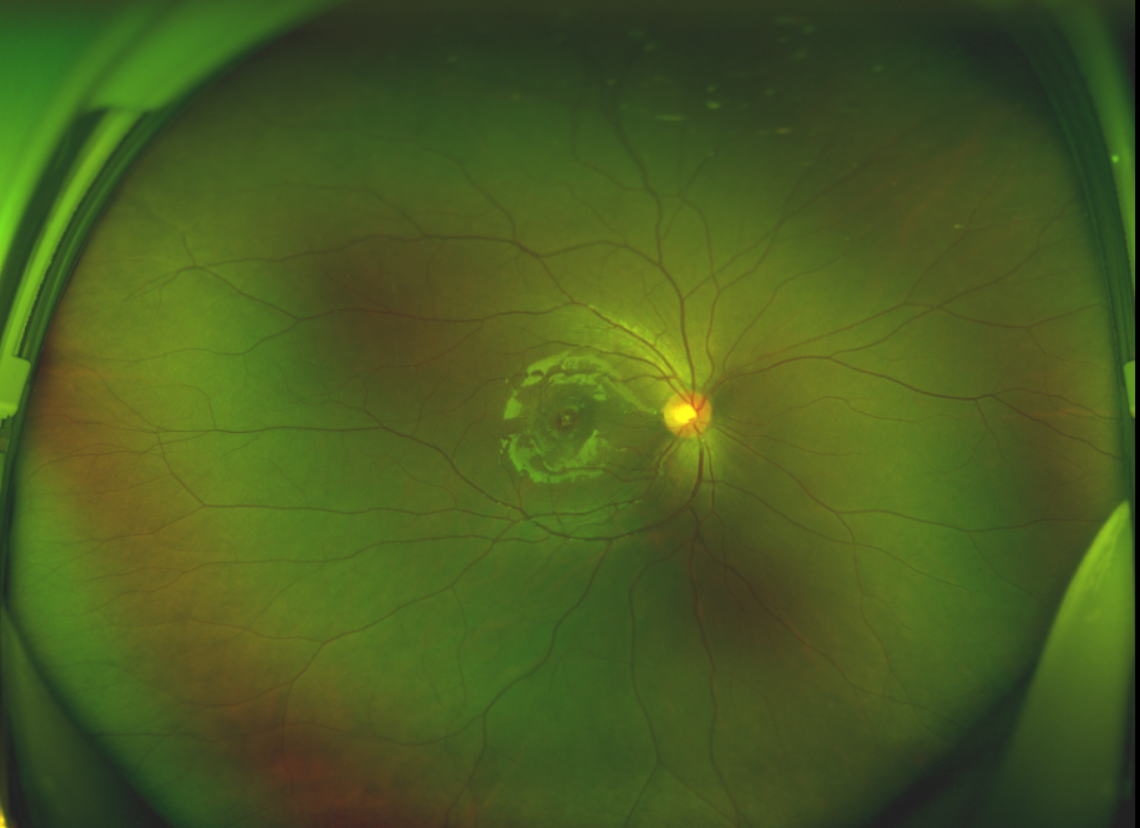

黃斑位于視網(wǎng)膜正中心,是視覺最敏銳的區(qū)域,堪稱“眼底的心臟”,負(fù)責(zé)我們閱讀、駕駛、識別人臉等精細(xì)視覺。 當(dāng)黃斑區(qū)的神經(jīng)組織出現(xiàn)全層缺損,形成一個“孔洞”,即為黃斑裂孔,它會直接導(dǎo)致中心視力急劇下降、視物變形、視野中心出現(xiàn)暗區(qū)。

經(jīng)過詳細(xì)的檢查和評估,王曉波主任決定采用“內(nèi)界膜翻轉(zhuǎn)覆蓋聯(lián)合粘彈劑固定術(shù)”為誠誠進(jìn)行治療。

術(shù)中,醫(yī)生精細(xì)剝離黃斑區(qū)的內(nèi)界膜后,并非直接丟棄,而是巧妙地給它翻個面,讓它變成一塊天然“創(chuàng)可貼”,嚴(yán)密覆蓋在黃斑裂孔的表面。覆蓋的內(nèi)界膜像微型支架一樣撐住裂孔邊緣,防止它擴(kuò)大;同時,這層膜本身含有能促進(jìn)生長的“養(yǎng)分”,能顯著刺激裂孔周圍的視網(wǎng)膜組織像爬山虎一樣快速生長、蔓延過來,最終把裂孔“補(bǔ)”好。

除此之外,利用自體組織覆蓋為黃斑裂孔提供了理想的愈合環(huán)境,裂孔閉合速度顯著快于傳統(tǒng)方法。誠誠接受手術(shù)24小時后,檢查可見內(nèi)界膜瓣位置良好;術(shù)后1個月,黃斑裂孔已經(jīng)閉合,視力恢復(fù)到0.5;術(shù)后兩個月,視力進(jìn)一步提升到0.7。